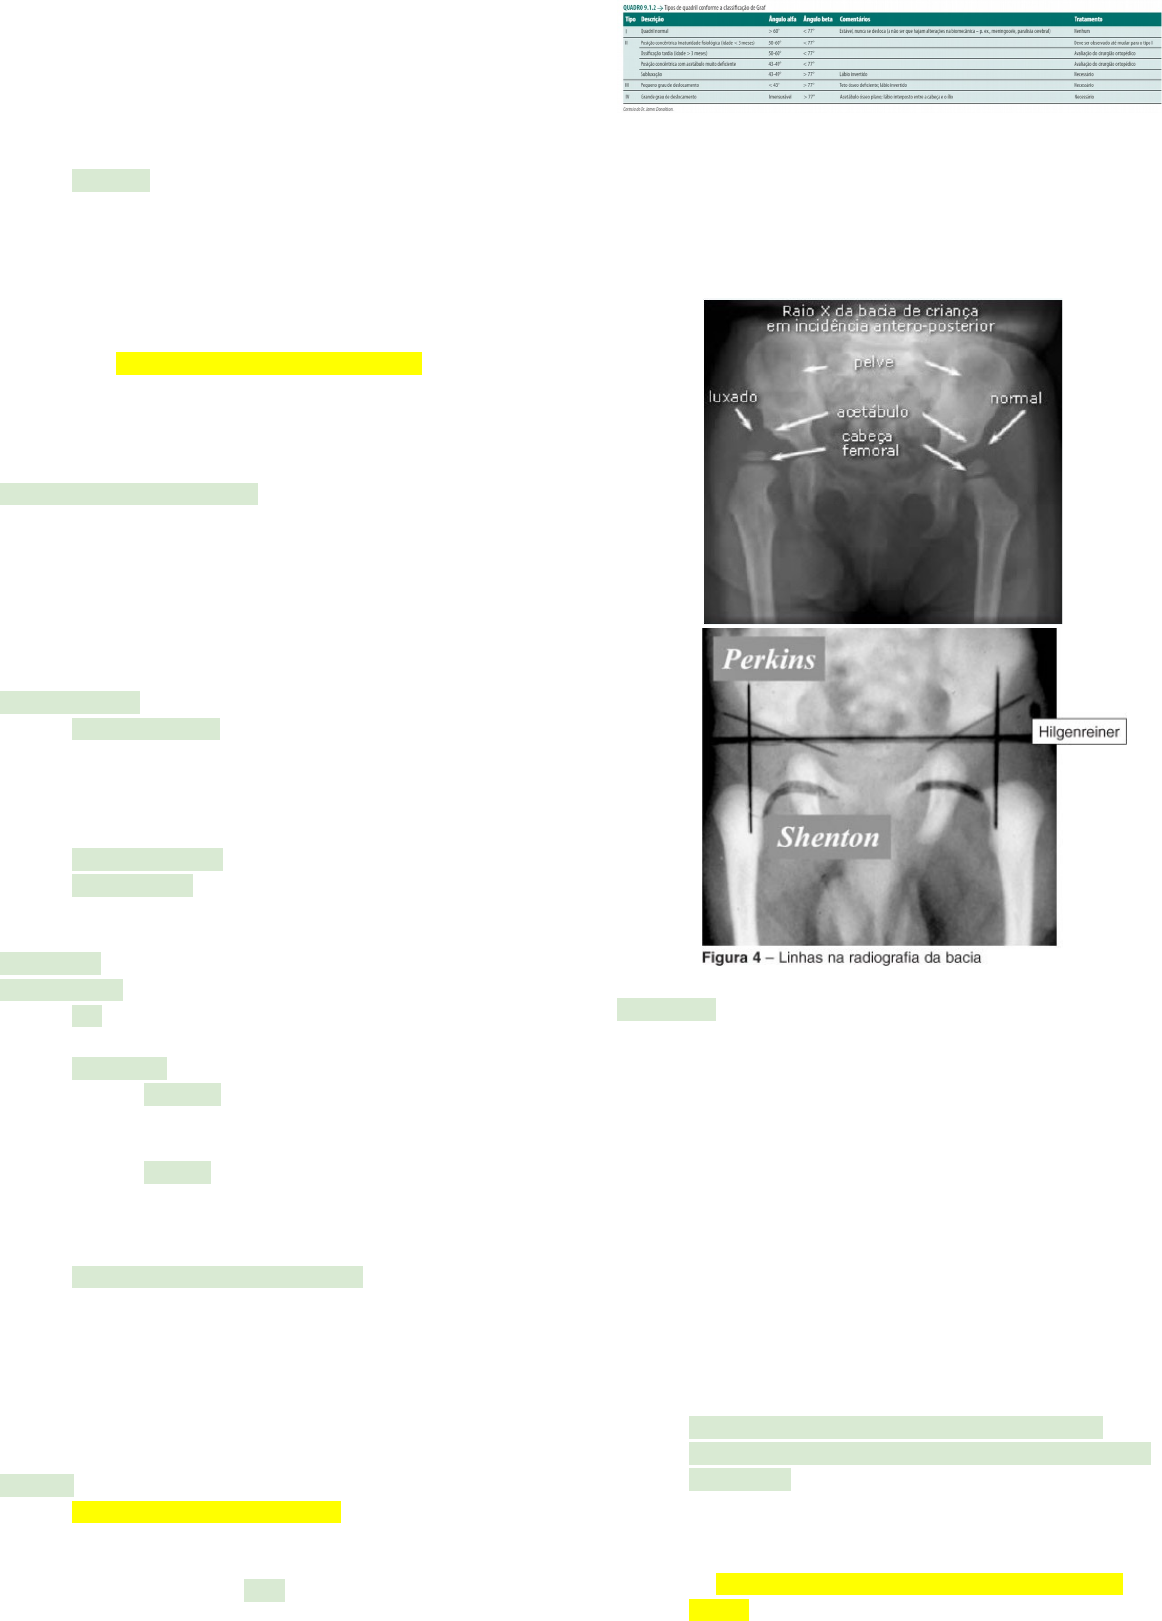

diagnóstico por imagem

· ultrassonografia: o quadril do recém-nascido é cartilaginoso, e a cabeça femoral não é visível ao raio X

· por isso, até os 6 meses de vida, é mais bem avaliado pela ultrassonografia, que identifica as estruturas cartilagíneas do acetábulo, da cabeça e do colo do fêmur

· dois métodos são usados para avaliar o quadril: o estático de Graf, que analisa o fêmur proximal e o contorno da pelve, e o dinâmico de Harcke, que emprega a ultrassonografia em tempo real, o que permite o exame dinâmico, com o quadril em movimento, fundamentando-se na reprodução das manobras de Barlow e Ortolani

· o método de Graf mede a displasia cartilagínea, e o de Harcke, a estabilidade do quadril